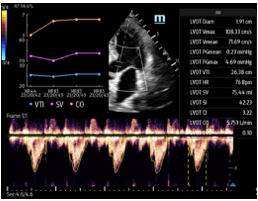

D1.  D2.

D3.

Figure D. In image D1, the TE7 Ultrasound machine is looking at the inferior vena cava (IVC). Image D2 shows the lung with ultrasound and D3 shows a cardiac assessment with smart measurements to check heart function. Images courtesy of Mindray Medical International.

Smart Velocity Time Integral (Smart VTI) – Automated Velocity Time Integral (VTI) and Cardiac Output (CO) measurements enable rapid cardiac function assessment. This software automatically locates the color box and Pulse Wave (PW) Doppler sample line in real-time. A graph of parameter trends for CO, Stroke Volume (SV), and VTI is produced to guide decision-making.

Smart Velocity Time Integral (Smart VTI) – Automated Velocity Time Integral (VTI) and Cardiac Output (CO) measurements enable rapid cardiac function assessment. This software automatically locates the color box and Pulse Wave (PW) Doppler sample line in real-time. A graph of parameter trends for CO, Stroke Volume (SV), and VTI is produced to guide decision-making.